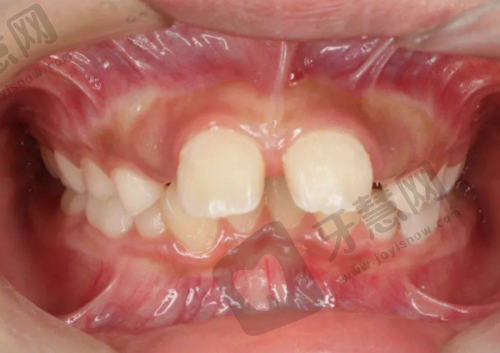

门诊部拥有一支专精的医生团队,医生们均毕业于有名口腔院校,具备扎实的专精知识。他们在各自擅长的领域有着丰富的临床经验,例如有的医生在牙齿矫正方面有着独特的见解和众多成功实例,有的医生在种植牙领域技术不错,能够根据患者的具体情况制定个性化的治疗方案。

众多患者对杭州艾维乾元口腔门诊部给出了良好的评价。患者们普遍反映在这里看牙体验良好,治疗成效显著。有的患者表示牙齿矫正后不仅牙齿变得整齐美观,而且咬合功能也得到了改善;还有患者称赞种植牙的成效逼真,使用起来和真牙无异,对门诊部的技术和服务都非常满意。